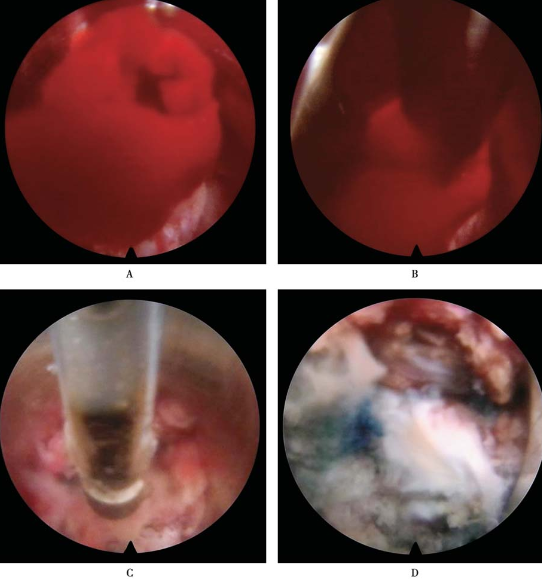

清理工作区:脊柱内镜置入,看到凝血块,小抓钳抓取,射频头止血、消融、探查,分离出工作区(图25)。

图25 清理工作区椎间孔镜置入A.看到血凝块;B.小抓钳抓取;C.射频头止血、消融、探查;D.分离出工作区

组织辨识转动工作套管,暴露突出物。

摘除突出髓核组织(图26)。

图26 摘除突出髓核组织

清理髓核组织碎片(图27)。

图27 清理髓核组织碎片

椎体后缘成形(图28)。

图28 L5椎体后缘

镜下完成标志:硬膜囊的波动及L5神经根减压游离,椎管内减压充分(图29)。

图29 镜下操作完成标志神经根漂浮试验阳性